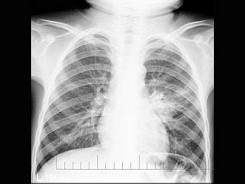

问题 三岁男孩,咳嗽、低热两周,不咯血、咳痰,X线检查如图,最可能的诊断是 ( )

选项 A、左肺结核(3型) B、以上都不正确 C、左肺结核(1型) D、左肺结核(2型) E、左肺炎症

答案 C